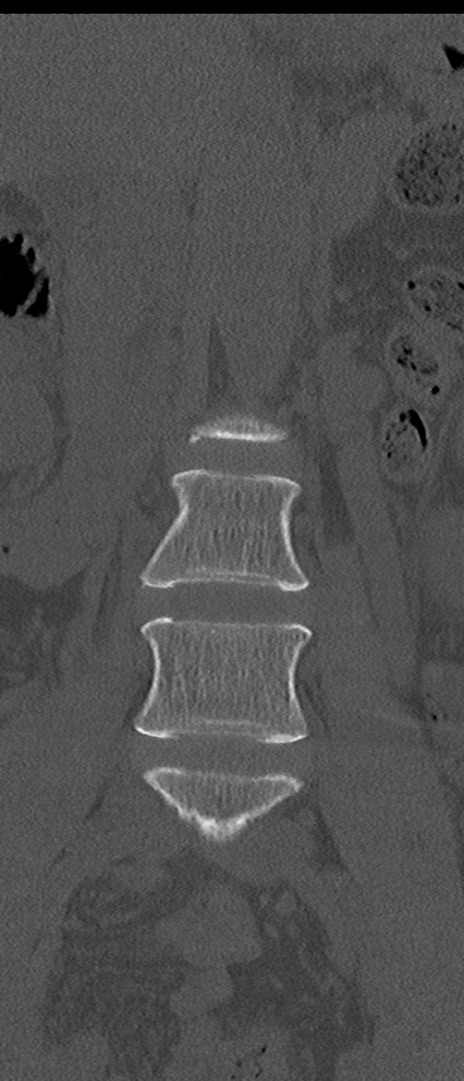

【整形】TIPS症例4 腰椎CT(冠状断像)

腰椎CT

矢状断像